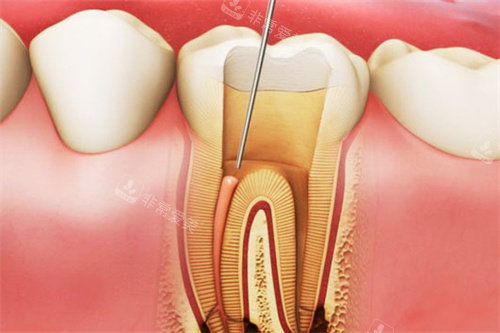

诊疗区域严格按照卫生标准进行设计和布局,每个治疗室都配备了可靠的口腔诊疗设备,如智能化口腔全景机、种植机等。

这些设备不仅能够提高诊断的比较准性和治疗的结果,还能减少患者的痛苦和治疗时间。